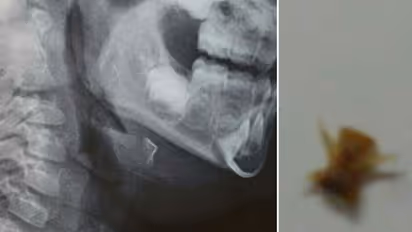

The parents then brought her to the SAT Hospital where an x-ray examination revealed that there was some obstruction in her respiratory track. A team of doctors then performed bronchoscopy under anaesthesia and identified the obstruction as fish bone and removed it, relieving the child of the breathing trouble.

'The big fish bone had blocked almost 50 per cent of the trachea (wind pipe). There was inflammation of the respiratory track due to which it had to be carefully removed', hospital sources said. Arushi used to take food on her own and would have inadvertently swallowed the fish bone, they added.